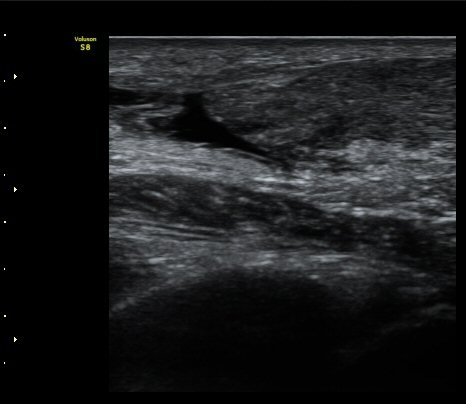

[¹ß¸ñ] ¾ÆÅ³·¹½º ÈûÁÙ ÆÄ¿­ÀÇ ÃÊÀ½ÆÄ Áø´Ü

ÁÂÃø ¹ß¸ñÀÇ ÅëÁõ(2ÁÖ)

2ÁÖ Àü ¹èµå¹ÎÅÏÇÏ´Ù°¡ ¹ß¸ñÀÇ ÅëÁõÀÌ ¹ß»ýÇÏ¿© Ÿº´¿ø¿¡¼­ ÃÊÀ½ÆÄ°Ë»ç µî ½ÃÇàÇÏ°í ºÎ¸ñ°íÁ¤ ÈÄ ¹°¸®Ä¡·á À§ÇØ ³»¿ø

¾ÆÅ³·¹½º°Ç ºÎÁ¾ ¹× ¾ÐÅë, ´Éµ¿Àû ¹ß¸ñ ¹ß¹Ù´ÚÃø ±¼°ñ G 1, thomson test(+).

ÃÊÀ½ÆÄ °Ë»ç